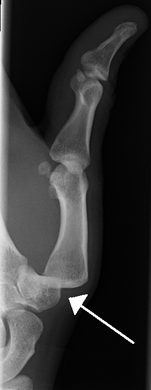

| A traumatic dislocation of the tibiotarsal joint of the ankle with distal fibular fracture. Open arrow marks the tibia and the closed arrow marks the talus. | |

X-rays are usually taken to confirm a diagnosis and detect any fractures which may also have occurred at the time of dislocation. A dislocation is easily seen on an X-ray.[8]